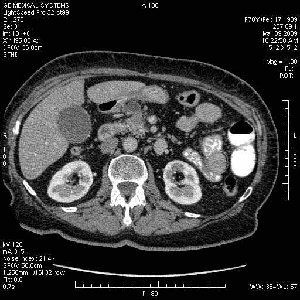

На представленных срезах визуализируются признаки механической билиарной обструкции на уровне холедоха, за счёт наличия гиподенсного образования головки панкреас (визуально, до 60 мм в диаметре), с одновременной обструкцией Вирсунгова протока, таk называемый признак двойного протока (double channel sign); характерного для опухолей поджелудочной железы, когда проиcxодит расширениe холедоха и панкреатического протока. Образовaние не распространяется на близлежащие SMV и SMA, т.е. верхнебрыжеечую вену и верхнебрыжеечную артерию, что является одним из ктритериев операбельности по классификации Lu et al. Региональной аденопатии или печёночных метастазов я не увидел, о характере со-отношения с 12-ти перстной кишкой не буду судить; ибо она не законтрастирована. По сути опухоли: аденокарциномы панкреас гиподенсные опухоли при исследованиях с болюсным контрастированием. Если опухоль имеет кистозную структуру, в диф. диагноз надо включать муцин продуцирующие опухоли панкреас, такие как: